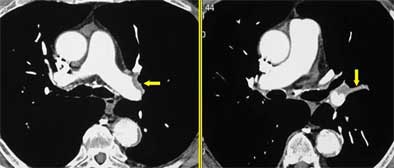

Organization: The organization of embolic material can be detected by the presence of partial or complete filling defects, Rémy-Jardin said. Unfortunately, the age of the thrombi cannot be determined by the presence of filling defects alone, so additional clues are needed to distinguish it from acute PE.

![]() |

| Organization of emblic material. All images courtesy of Dr. Martine Rémy-Jardin. |

Recanalization: Within the artery, the radiologist can readily detect the recanalization channels, filled with blood that has been opacified by the contrast material. The channels tend to be located very near the areas of nonperfusion due to chronic obstruction, and the presence of focal stenoses can be indicative of recanalization, she said. In addition to transverse sections, additional reformations in the coronal and sagittal planes can often be helpful in delineating the morphology of the channels. "When the stenoses are in the plane of reformation, they are not easily detected in transverse sections," Rémy-Jardin said.

| Recanalization of embolic material. |